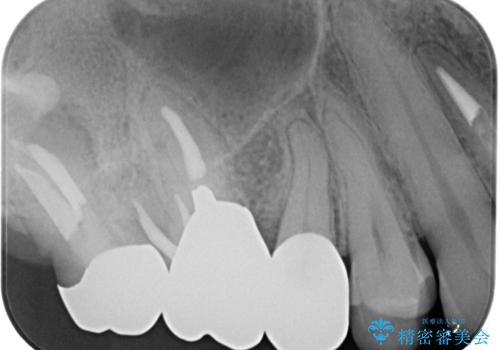

- 「右上の第一小臼歯の詰め物が外れてしまった」という主訴でご来院されました。

診査したところ、既存の詰め物の一部が欠け、歯と詰め物の境目にも段差がある状態で、再度詰め直しが必要でした。

まず残っている詰め物をすべて丁寧に除去し、二次カリエスがないかを確認したうえで、形を整えました。